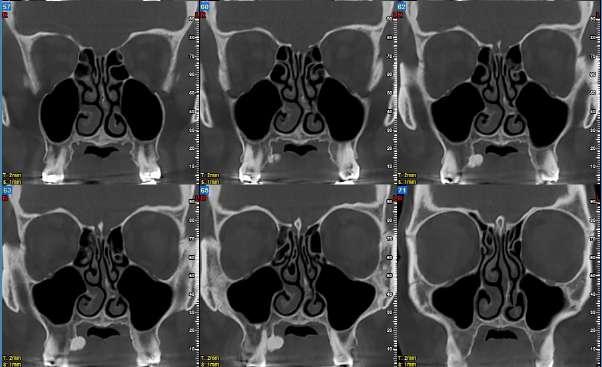

12.00 L’in uenza del genere nell’espansione scheletrica del palato, valutazione CBCT dello stadio di ossi cazione della sutura palatina mediana

Federica Altieri, Martina Mezio, Michele Cassetta